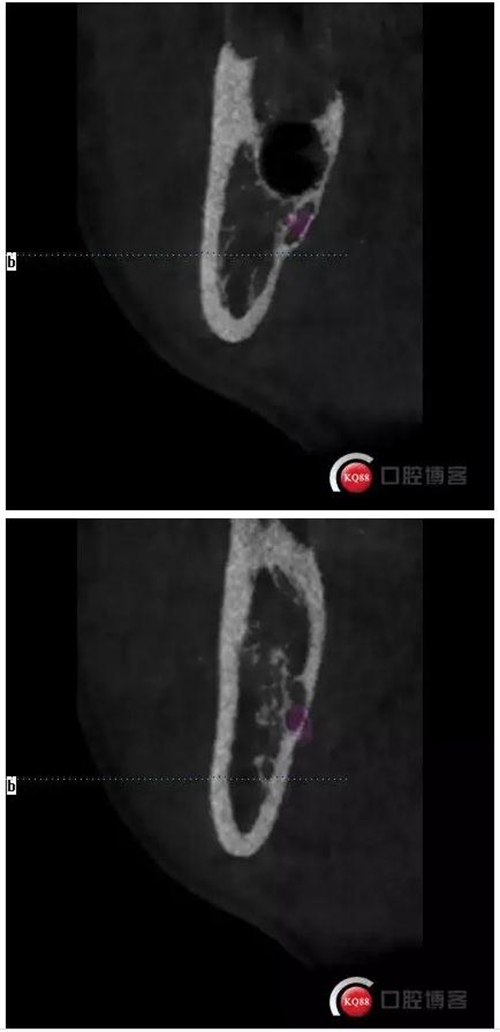

口內(nèi)照片,48遠(yuǎn)中三分之一覆蓋部分牙齦。

拔牙創(chuàng)口,清理周邊肉芽,切忌,不能搔刮。

縫合。

檢查。

拔牙后拍片檢查。